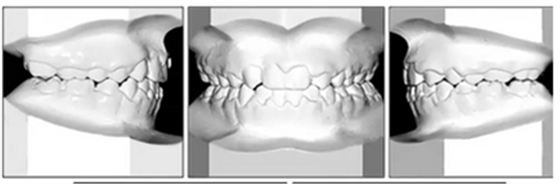

總體治療目標(biāo)已經(jīng)實現(xiàn)。病人的笑容和輪廓有所改善。咬合關(guān)系為I類磨牙關(guān)系,牙列整齊,牙尖交錯關(guān)系良好。反合和中線偏移得以矯正,并實現(xiàn)了正常的覆蓋和覆合。上下牙弓的擁擠問題完全解決,并且完成后全景片顯示良好的牙根傾斜度。疊加顯示良好的縱向和垂直控制(ANB,3.5°; SN / GoMe,42.5°)和矯正上下頜前牙傾斜度(1 / SN,96°; IMPA,87°)(圖10 ; 表)。

經(jīng)過24個月的保持后,咬合保持得很好(圖11 ; 圖12)。在上牙弓中,應(yīng)用固定舌側(cè)保持器以防止任何復(fù)發(fā)傾向。在下牙弓中,治療后拔除第三磨牙。